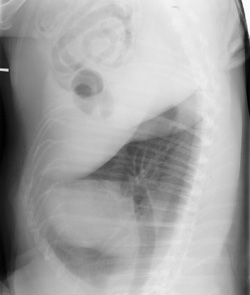

Film folded in cassette during exposure (double image)